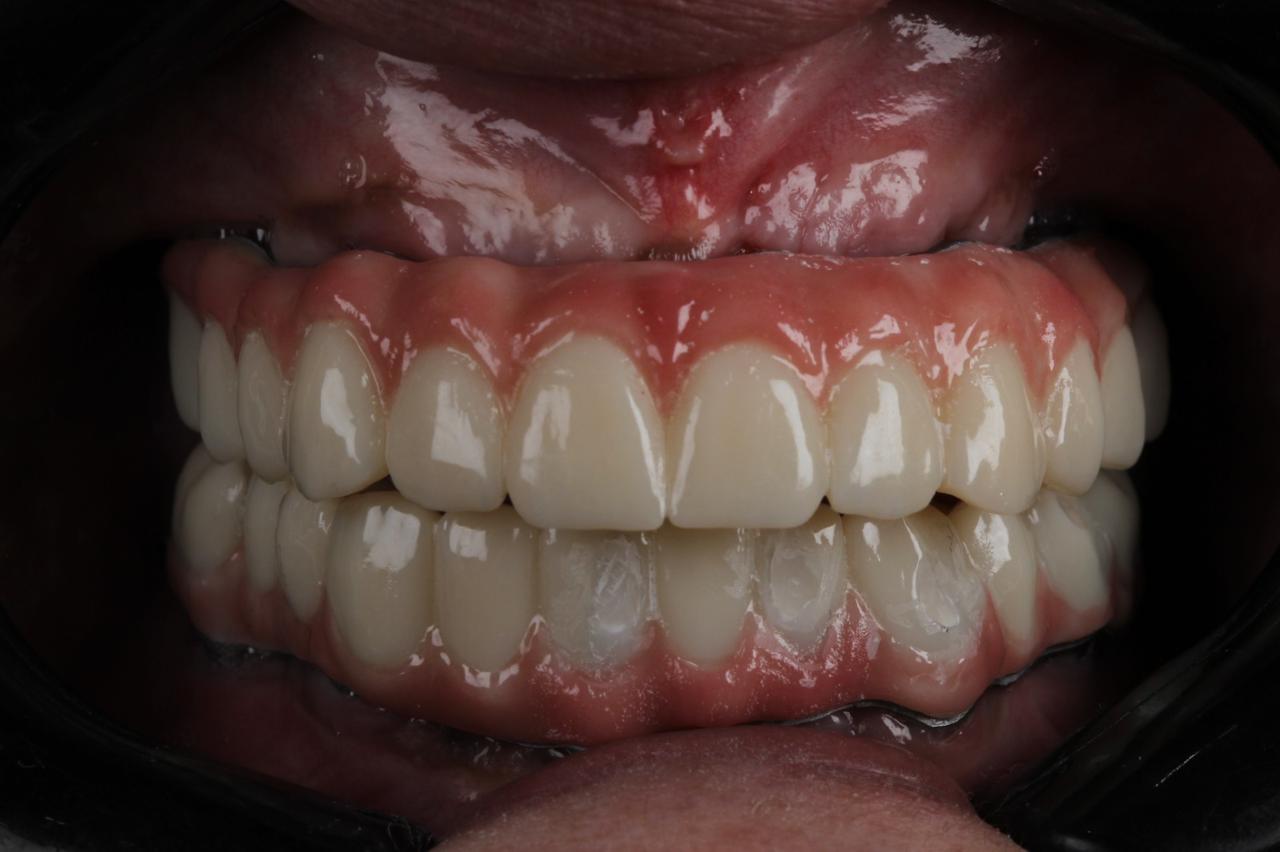

زراعه الأسنان